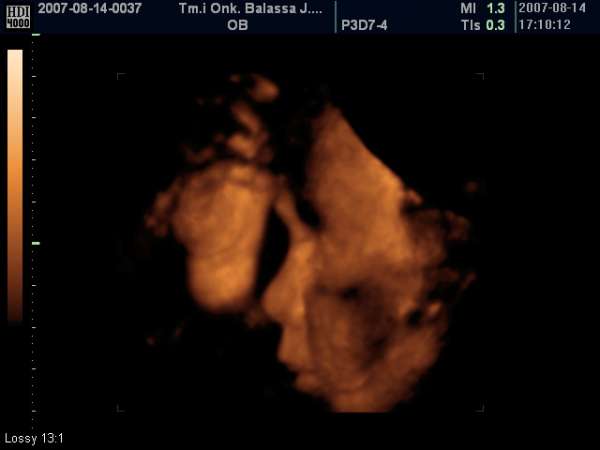

bocsi lányok,a doki csak hat körül jött le,szülőszobán volt,utána még boltba kellett mennünk. Nagyon édes képet csinált a pofijáról,amit képzeljétek el,alul talált meg :D

Kép

És a kép :D ...a pofija mellett az a valami az egyik talpa :lol: